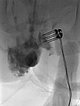

Nach Sicherung der Diagnose erfolgte jetzt die Therapie in Form einer Bleomycin Elektrosklerotherapie. Hierzu wurde die venöse Malformation zunächst mit jeweils einer Nadel unter Ultraschallsteuerung auf beiden Seiten punktiert und mit Kontrastmittel injiziert. Gute Nadellage, es finden sich keine größeren Drainagevenen.

Über die beiden liegenden Nadeln wurde jetzt insgesamt 0,75 mg Bleomycin (eins zu drei in Kontrastmittel verdünnt) in die venöse Malformation direkt intraläsional injiziert. Anschließend auf beiden Seiten insgesamt zusammen 11 Applikationen einer reversiblen Elektroporation mit der Fingerelektrode mit 15 mm aktiver Nadellänge.